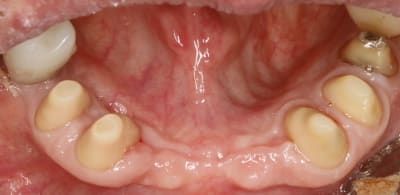

tourne et vire y a que ça qui me plait , le bridge de contention du bas .

toutes les dents qui bougent à mort , les incisives qui se font la malle , les gencives explosées et gros pb occlusal bien sur .

apres extractions et endos zing zing les tailles .

ici les tailles ont duré 3 mois pour en arriver là .

Chouette et propre ta gencive

3 mois :-) c était un choux-fleurs violet au départ .

3 mois pour tailler .

non , on va le dire différemment, 3 mois pour arriver au niveau des limites définitives .

Chaques fois un petit coup pour arriver au niveau gingival cicatriciel du jour .

4 fois y compris les prétailles en unitaire avant les extractions de 41,42, 31,32 et 46

dans les 4 fois , en plus des tailles des moignons en totalité je compte aussi les tailles des racines et de gencive qui me permettent de faire de l assainissement parodontal .

Ici les préparations sont trop coniques, et 4 tailles c’est 4 agressions pulpaires…